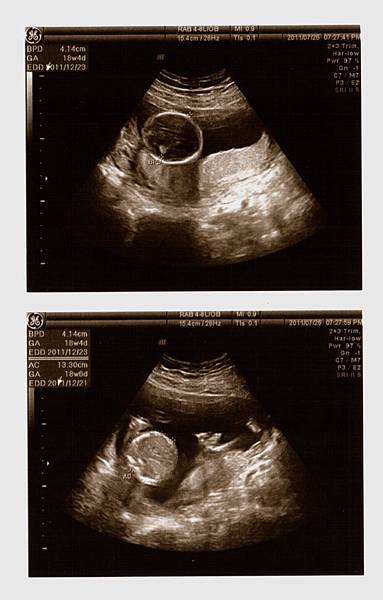

接著,重頭戲來囉,黃醫師幫我照了超音波,躺在床上的我和站在一旁的老公顯得緊張,當我還在思考等一下醫生會告訴我寶寶究竟是男是女之際,思路還來不及轉彎之時,黃醫師就已迅雷不及掩耳的速度告訴我:『這是男寶寶喔!』我驚訝的不得了!還說『怎麼看啊?在哪在哪?』醫生不急不徐地說:『這是寶寶的弟弟,有看到凸出來的,那就是弟弟喔!』天啊,是弟弟啊(說實在,我真想看看老公當時的表情><)接著,醫師告訴我寶寶的頭偏大,看來是個大頭弟,大腿骨普通長(媽媽我還以為他是個長腿男勒!),然後醫師拿著探頭四處看,告訴我寶寶的一切都正常,讓媽咪我放心了許多!

一連串拿了七張超音波照片,還看了4D的超音波,真是超棒的唷!!!